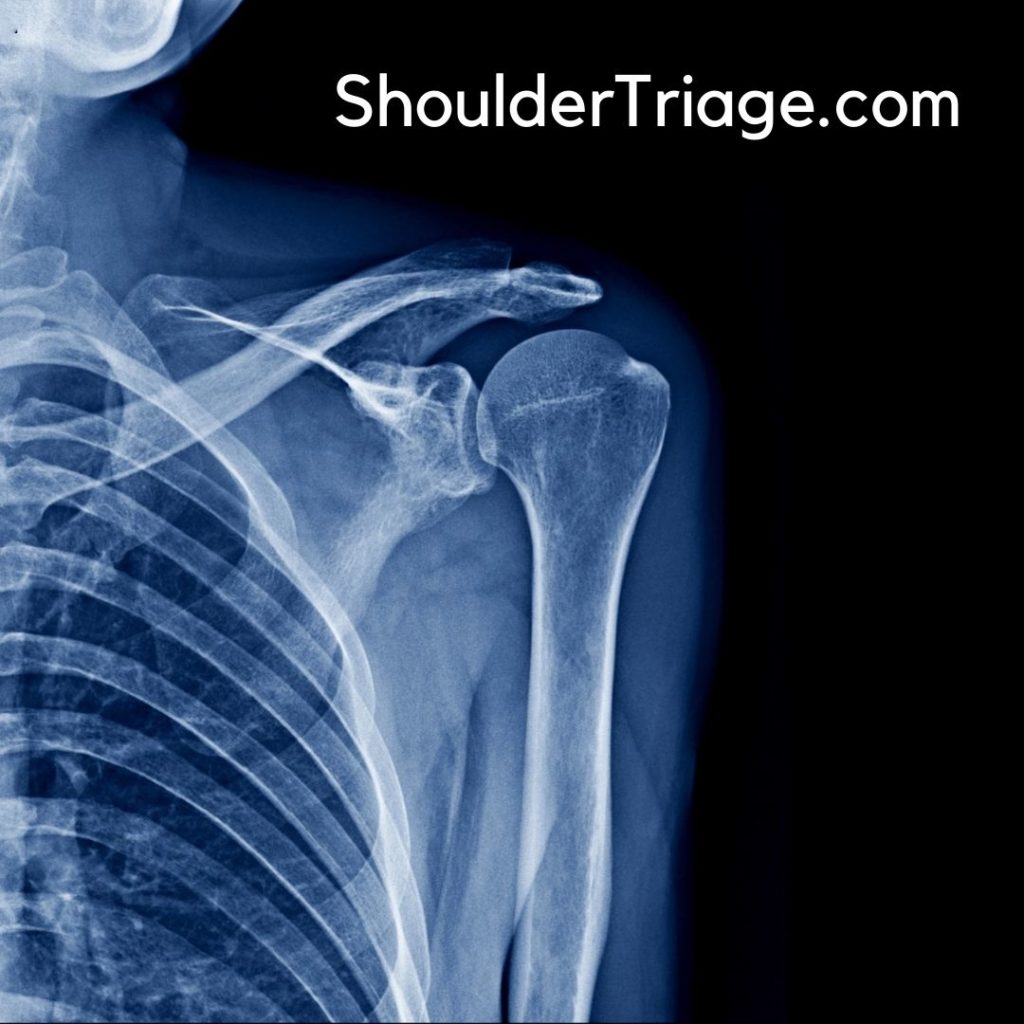

1. X-ray (First-Line Imaging)

- AP and lateral views are essential.

- Axillary view helps confirm dislocations.

- Scapular Y view is useful for posterior dislocations.